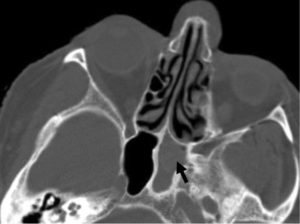

КТ — исследование пазухи с помощью рентгеновского излучения. КТ позволяет выявить аномалии синуса, степень поражения слизистой. При исследовании с помощью КТ определяется уровень гноя в пазухе.

Ещё более информативным методом диагностики является МРТ — она выявляет послойные поражения, которые могут быть не замечены на КТ.